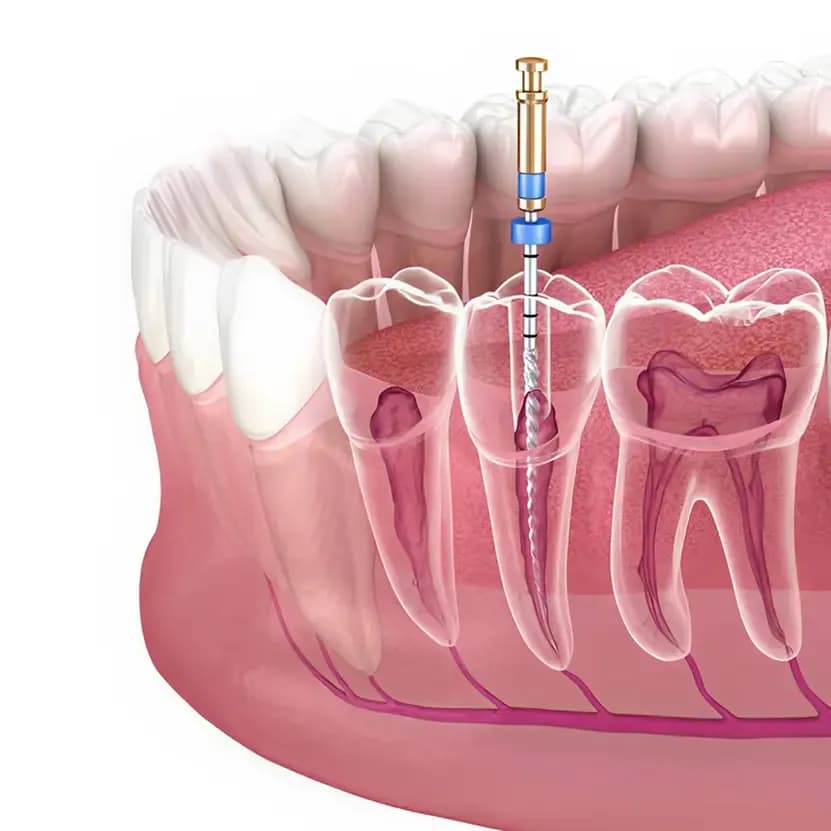

- Access Opening A small opening is made in the crown of the tooth to gain access to the pulp chamber and root canals.

- Pulp Removal & Canal Cleaning The infected pulp tissue is carefully removed, and each root canal is meticulously cleaned, shaped, and disinfected.

- Canal Filling The cleaned canals are filled with a biocompatible material called gutta-percha and sealed with adhesive cement to prevent re-infection.